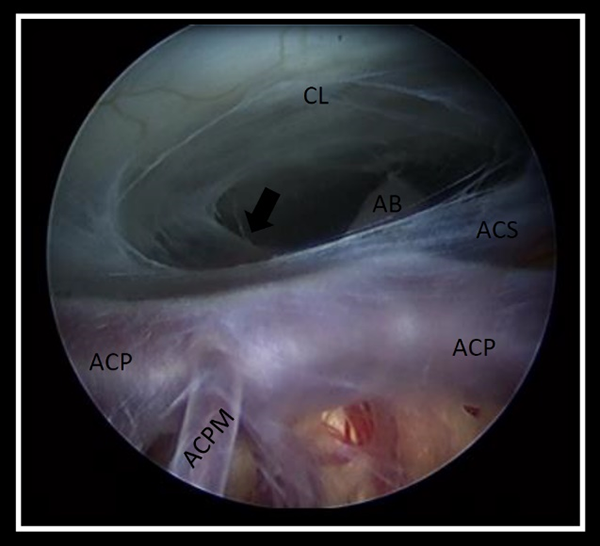

Al realizar el análisis de las grabaciones, la ostomía se consideró satisfactoria si: a) el diámetro permitió el pasaje del endoscopio, y así corroborar la correcta disección de la membrana de Liliequist, objetivando la exposición de la arteria basilar y algunas de sus ramas principales, b) visualización del movimiento ondulante de los bordes libres de la ostomía por el paso del LCR (Figura 1).

Figura 1. Imagen endoscópica obtenida desde la ostomía que permite observar la disección correcta de la membrana de Liliequist (flecha), objetivando la exposición completa de la arteria basilar y sus ramas principales. AB: arteria basilar, ACS: arteria cerebelosa superior, ACP: arteria cerebral posterior, ACPM: arteria central posteromedial izquierda CL: clivus.